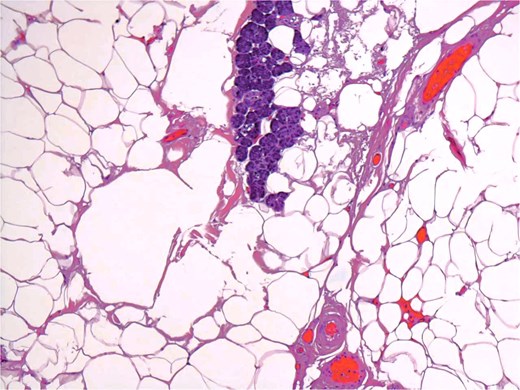

A 54-year-old male presented for assessment of a non-tender swelling in the left parotid region. His past medical history was unremarkable. Neck magnetic resonance imaging (MRI) revealed a well-defined adipose lesion in the left parotid gland measuring nearly 4.6 cm in its largest dimension. Neck ultrasound (US) additionally revealed bilateral thyroid nodules; Fine-needle aspiration of the right thyroid nodule confirmed benign follicular changes (Bethesda class II). Follow-up imaging (MRI and US) 1 year later showed a stable parotid lesion measuring 5.3 × 3.2 × 2.8 cm without contrast uptake. Bilateral thyroid nodules were unchanged. The patient was asymptomatic but reported cosmetic worries. Repeat imaging MRI demonstrated mild progression to 4.8 cm, expanding toward the parapharyngeal space. The lesion displayed uniform fat signal with no malignant enhancement. In view of gradual enlargement and patient cosmetic concern, surgical excision was recommended. A complete left parotidectomy with full general anesthesia was performed. During surgery, a lobulated, soft tumor measuring 6 × 4.5 × 2 cm was excised, while sparing all facial nerve branches. No complications were noted. Microscopic examination revealed a lobulated fibro-fatty tumor consisting of well-differentiated adipose tissue with intermixed salivary gland acini and ducts (Figs 1 and 2), establishing the diagnosis of sialolipoma. Postoperative recovery occurred without complications, and the patient showed normal facial nerve function at follow-up.

Groups of acini and occasional ducts present within the lipomatous tumor.